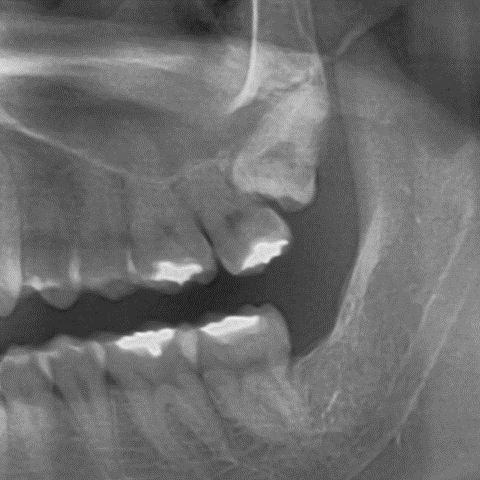

상악 치열을 뒤로 이동시키기 위해서는 일반적으로 사랑니 발치가 먼저 필요합니다.

하지만 이번 증례에서는 좌측 제2대구치의 상태가 좋지 않았습니다.

이 경우, 사랑니를 빼고 제2대구치를 유지하는 것보다

오히려 제2대구치를 발치하고 사랑니를 그 자리에 배열하는 전략이 더 효율적일 수 있습니다.

왜냐하면 기존 제2대구치를 이상적인 위치까지 이동시키려면

치아 몸체뿐 아니라 뿌리까지 많은 이동이 필요해 치료 효율과 안정성 측면에서 불리할 수 있기 때문입니다.